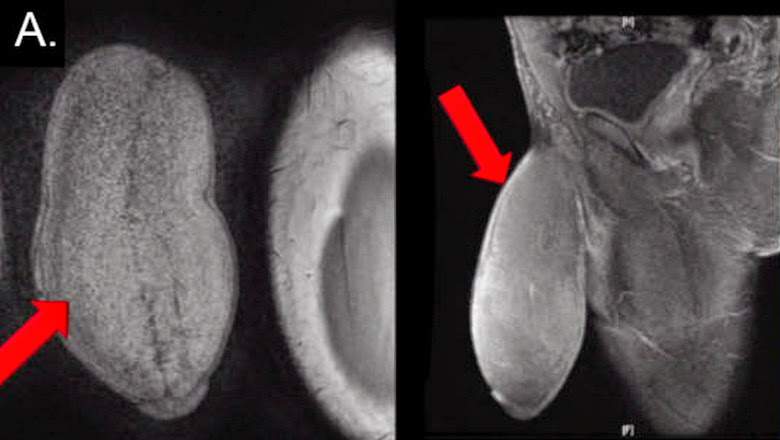

Jovem faz cirurgia para diminuir tamanho do pênis